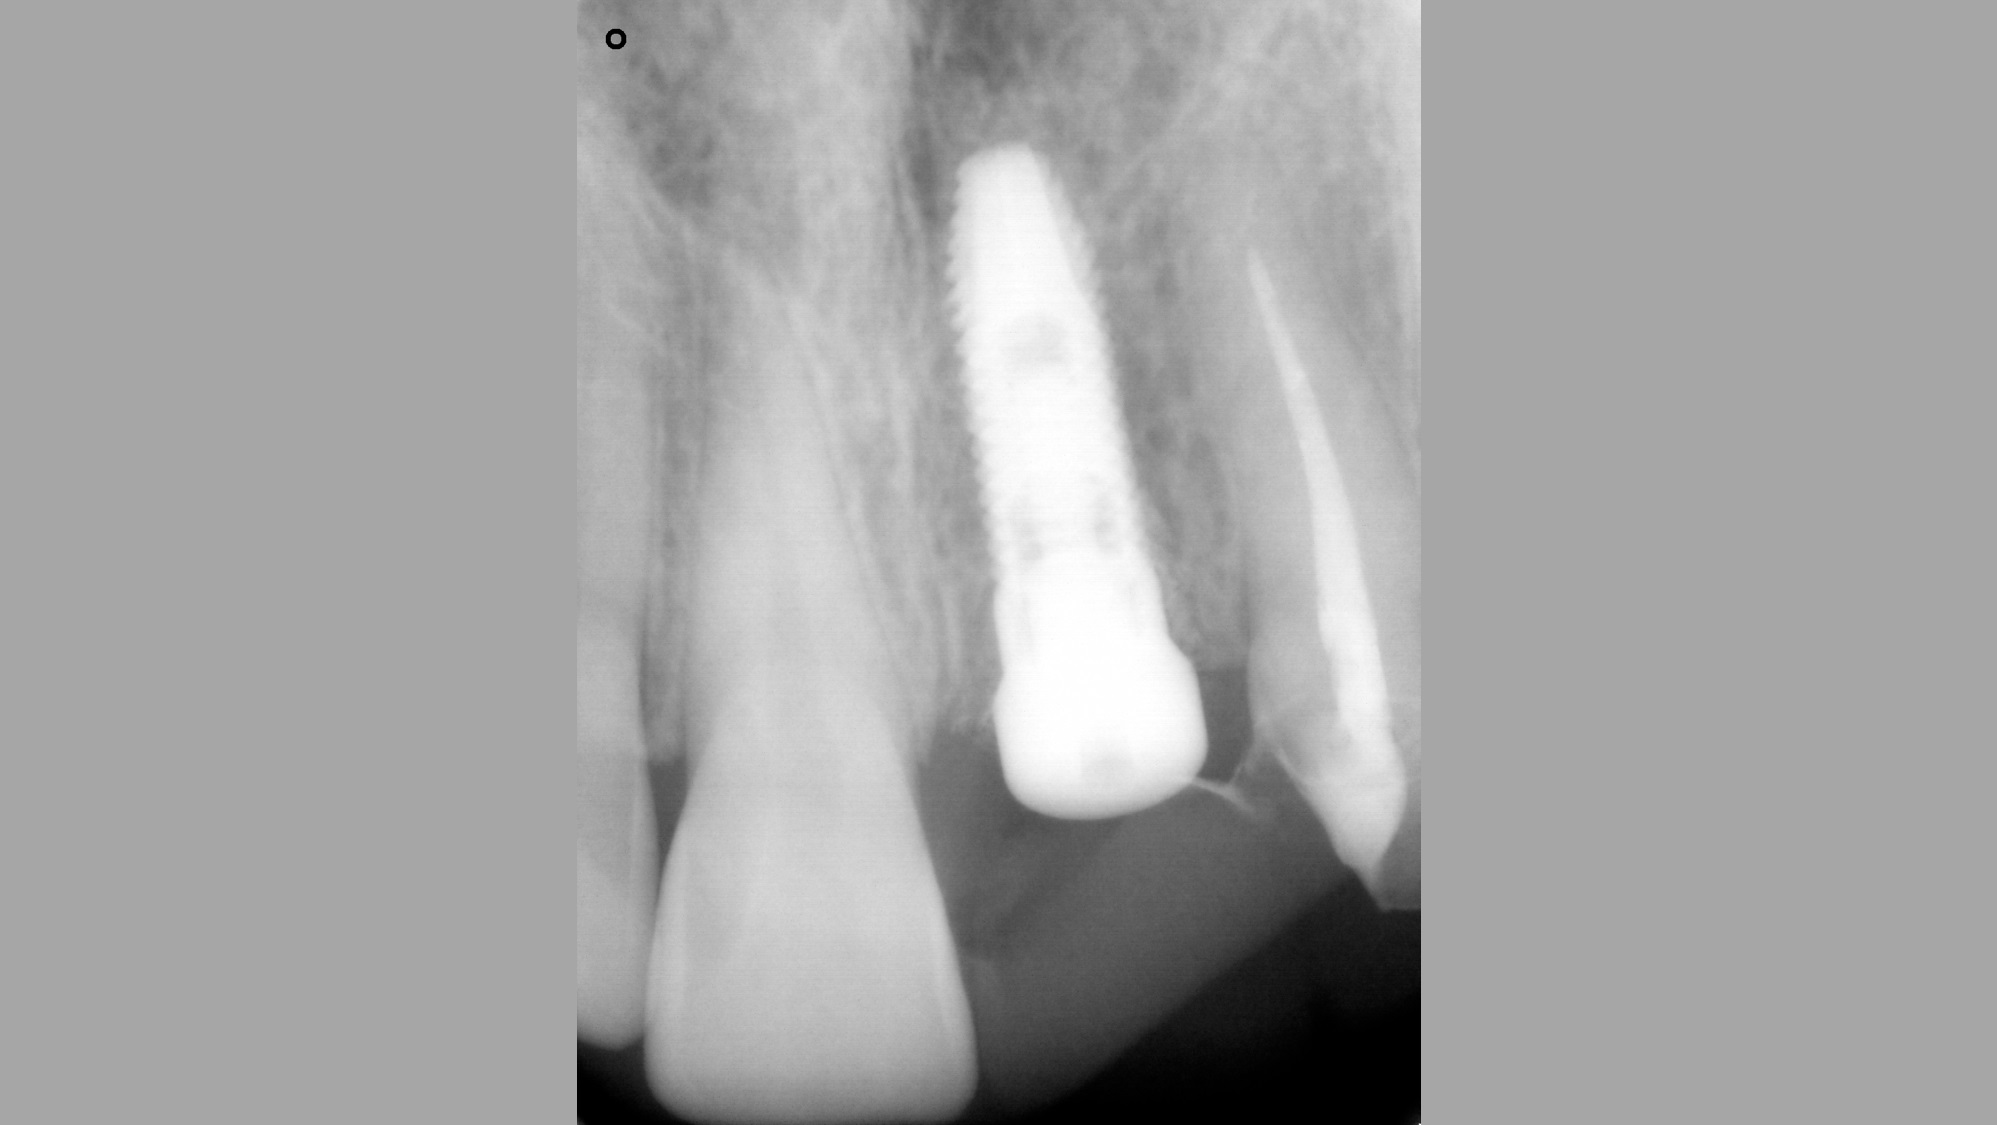

03/16 - Radiograph befor extraction of 21

Socket preservation with cerabone® - Dr. R. A. Nader